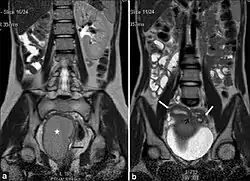

عادةً ما تُشخص الحالة عبر التصوير بالرنين المغناطيسي أو الموجات فوق الصوتية. يُوصى باستشارة أخصائي طب نساء في هذه الحالة.